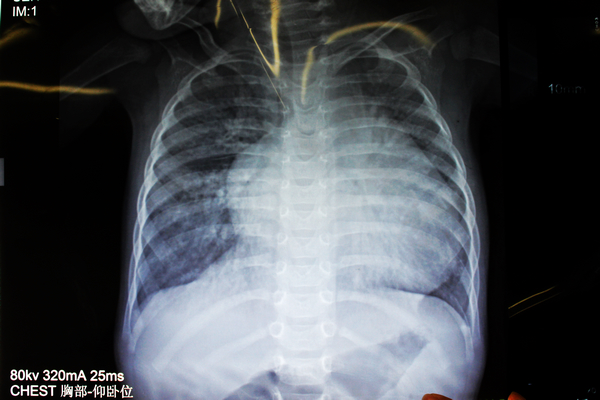

“别以为她的人小,心脏就跟着小,因为患了严重的心脏病,小鑫怡心脏却大得像个大大的皮球!”在心胸外科医生办公室,杨柳山副主任医师向笔者展示了小鑫怡的X光胸片,只见小小的胸腔里,一团白色心脏阴影几乎占满了半个胸部的视野,那是小鑫怡的心脏,就是这颗发育异常的心脏,让小鑫怡降临到这世上的10个多月里,吃尽了苦头。

小鑫怡术前的X光胸片,可以看到心脏大得像个球